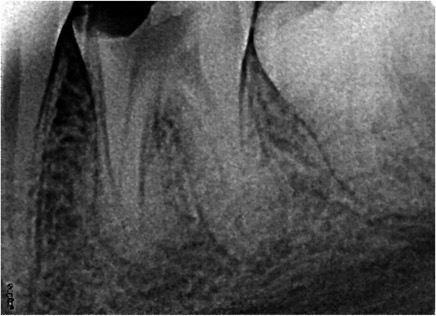

A 25 years old female came with the complaint of pain and sensitivity in mandibular left first molar (Figure 2). After clinical and radiographic examination and endodontic therapy was advised.  After anaesthetizing the tooth, access preparation was done and canal orifices were located with DG 16 endodontic explorer. Initial negotiation of the root canals was performed with K-file # 10. Thereafter GenEndo files were used in a sequential order as per the manufacturer’s instructions.  CF file (Coronal Flare file) was first used to perform the coronal flare. Thereafter, 10 K-file was used to measure the working length using an electronic apex locator (Canalpro, Coltene). Thereafter, GPF was used up to the WL in order to make a smooth glide path for the larger files to follow. Subsequently, the PF and UFI were used in the sequential order up to the WL to complete the preparation. Warm 5 % sodium hypochlorite (warmed using Syringe warmer, Coltene) was used throughout the procedure as the irrigant. Calcium hydroxide was given as intracanal medicament. In the next appointment, as the patient was asymptomatic,  master cone fit radiograph was taken  using corresponding GP Points (GenENDO) which  revealed proper fitting of respective GP cones. Canals were dried with paper points and obturation done by using single cones of corresponding taper and size as MAF, using Gutta Flow Bioseal sealer (Coltene). The fine and curvy mesial canals and two distinct distal canals in this tooth can be easily appreciated (Figure 3).

Figure 2 Pre-operative radiograph of mandibular first molar.